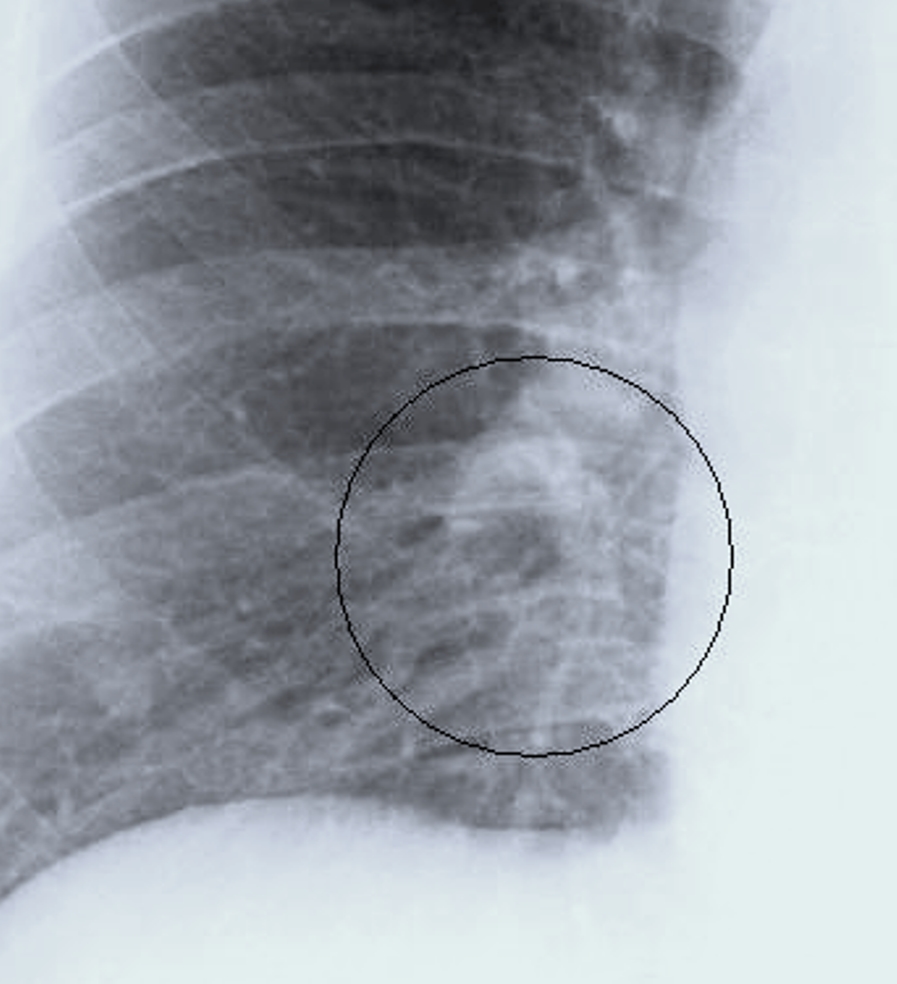

Рентгенодиагностика бронхопневмонии: Советы и примеры

Раздел: Альбом открытий